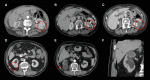

Objectives: To assess the safety and efficacy of percutaneous microwave ablation (MWA) of histologically proven T1 renal cell carcinoma (RCC).

Methods: We analysed patients with a histologically proven RCC (≤ 7 cm) treated by MWA from April 2012-April 2018. Primary and secondary efficacy, local tumour recurrence (LTR), morbidity and mortality were reported. Efficacy was defined as no residual tumour enhancement on follow-up imaging 1 month after the first ablation (primary efficacy) and after re-ablation(s) for residual disease (secondary efficacy). Adverse events (AE) were registered by the Clavien-Dindo classification and the common terminology criteria for AE. Univariable and multivariable logistic regression analyses were performed to investigate a relation among pre-treatment factors incomplete ablation and complications.

Results: In 100 patients, a total of 108 RCCs (85 T1a and 23 T1b) were treated by MWA. Median size was 3.2 cm (IQR 2.4-4.0). Primary efficacy was 89% (95%CI 0.81-0.94) for T1a lesions and 52% (95%CI 0.31-0.73) for T1b lesions (p < 0.001). Fifteen lesions (7 T1a) were re-ablated for residual disease by MWA in one (n = 13) and two (n = 2, both T1b) sessions resulting in secondary efficacy rates of 99% (T1a) and 95% (T1b, p = 0.352). LTR occurred in four tumours (2 T1a, 2 T1b) after 10-60 months. Six (4%) AEs grade > 3-5 were observed (2 T1a, 4 T1b, p = 0.045). Multivariable analysis showed that mR.E.N.A.L. nephrometry was independently associated with incomplete ablation (p = 0.012).

Conclusion: Microwave ablation is safe and effective for T1a and T1b RCC lesions with a significantly lower primary efficacy for T1b lesions.